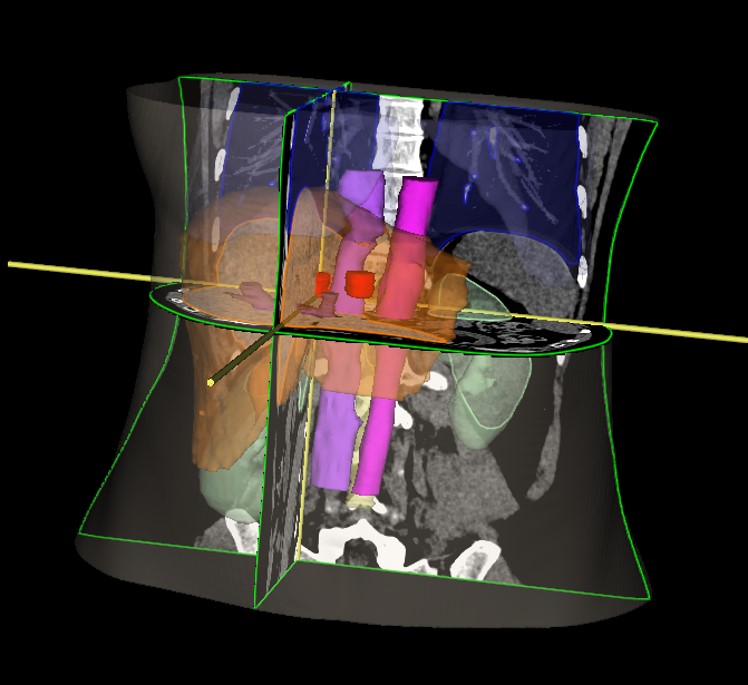

SABR meta hepatis et pelvis (21.11.2017.)

Rezultat – 47 mjeseci nakon RK

potpuni nestanak tretiranih lezija